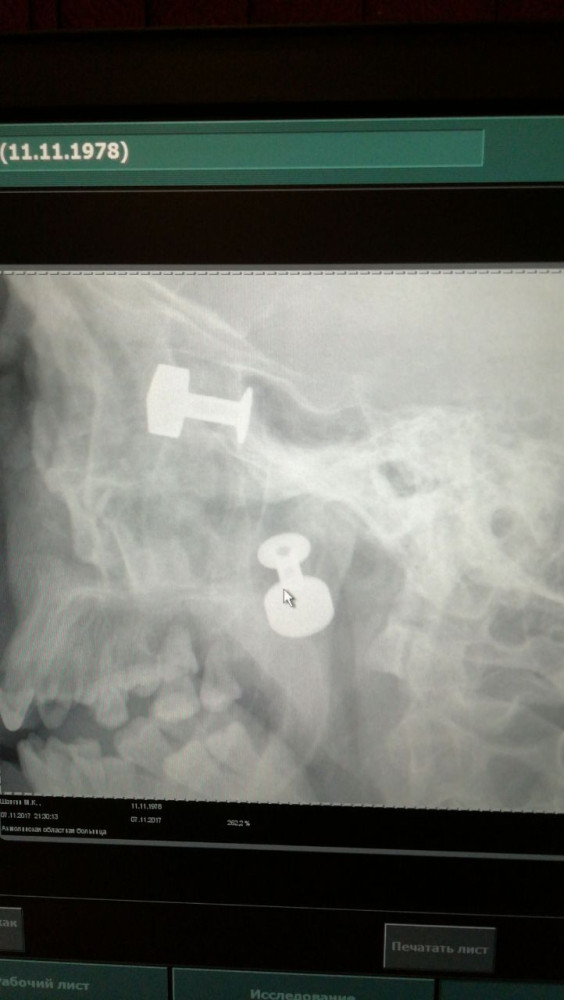

«Похоже, стреляли из близкого расстояния, практически в упор. Мы не знаем, но примерно так. Он говорил, что не помнит обстоятельства произошедшего. Наше дело – спасать. Когда сделали снимок головы, ужаснулись: три пули, одна из которых прошла по касательной, не задев жизненно важные ткани», - рассказал заведующий отделением челюстно-лицевой хирургии облбольницы Владимир Митчинов.

Операция по извлечению двух других пуль длилась больше двух часов, работали врачи лор-отделения и челюстно-лицевой хирургии. Операция без надрезов, относится к высокотехнологичным, с применением новейшей аппаратуры – эндоскопической лор-стойки, производства Германии.

«Случись это раньше, когда еще не было такой аппаратуры, нам бы пришлось сделать доступ, и довольно большой, чтобы найти и извлечь эти пули. А это, во-первых, опять же риск для жизни, во-вторых, длительная и тяжелая реабилитация. Сложность в том, что обе пули застряли очень близко от головного мозга. Там рядом сосуды, нервы. В лучшем случае пациент мог зрение потерять, в худшем – погибнуть. А так мы при помощи эндоскопа и специальных медицинских инструментов, не рассекая ткань, проникли на глубину где-то 10 см и через раневой канал извлекли пули. Найти их тоже было сложно, потому что она дает деформацию тканей, отек, смещение», - рассказал заведующий лор-отделением Арман Нагуманов.